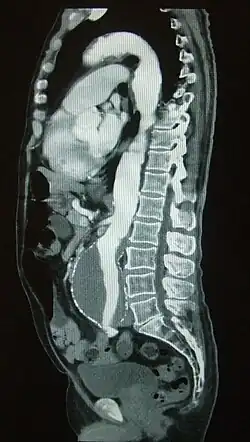

Seguimiento de un bolo de contraste en su paso por la arteria aorta evidenciándose un aneurisma aórtico.

En la angiografía por TAC, el análisis se realiza simultáneamente con una inyección de medios de contraste a alta velocidad hasta que alcance el lecho arterial de interés, empleando una técnica que le hace seguimiento a la trayectoria del bolo inyectado.[1]​ En comparación con la angiografía por catéter, que consiste en colocar un catéter de calibre importante e inyectando a través de éste el material de contraste dentro de una gran arteria o vena, la angiografía por TAC es mucho menos invasiva y menos incómoda para el paciente. El material de contraste se inyecta en una vena periférica mediante el uso de una pequeña aguja o cánula intravenosa. Este tipo de examen se ha utilizado para examinar a un gran número de personas en busca de enfermedades arteriales.